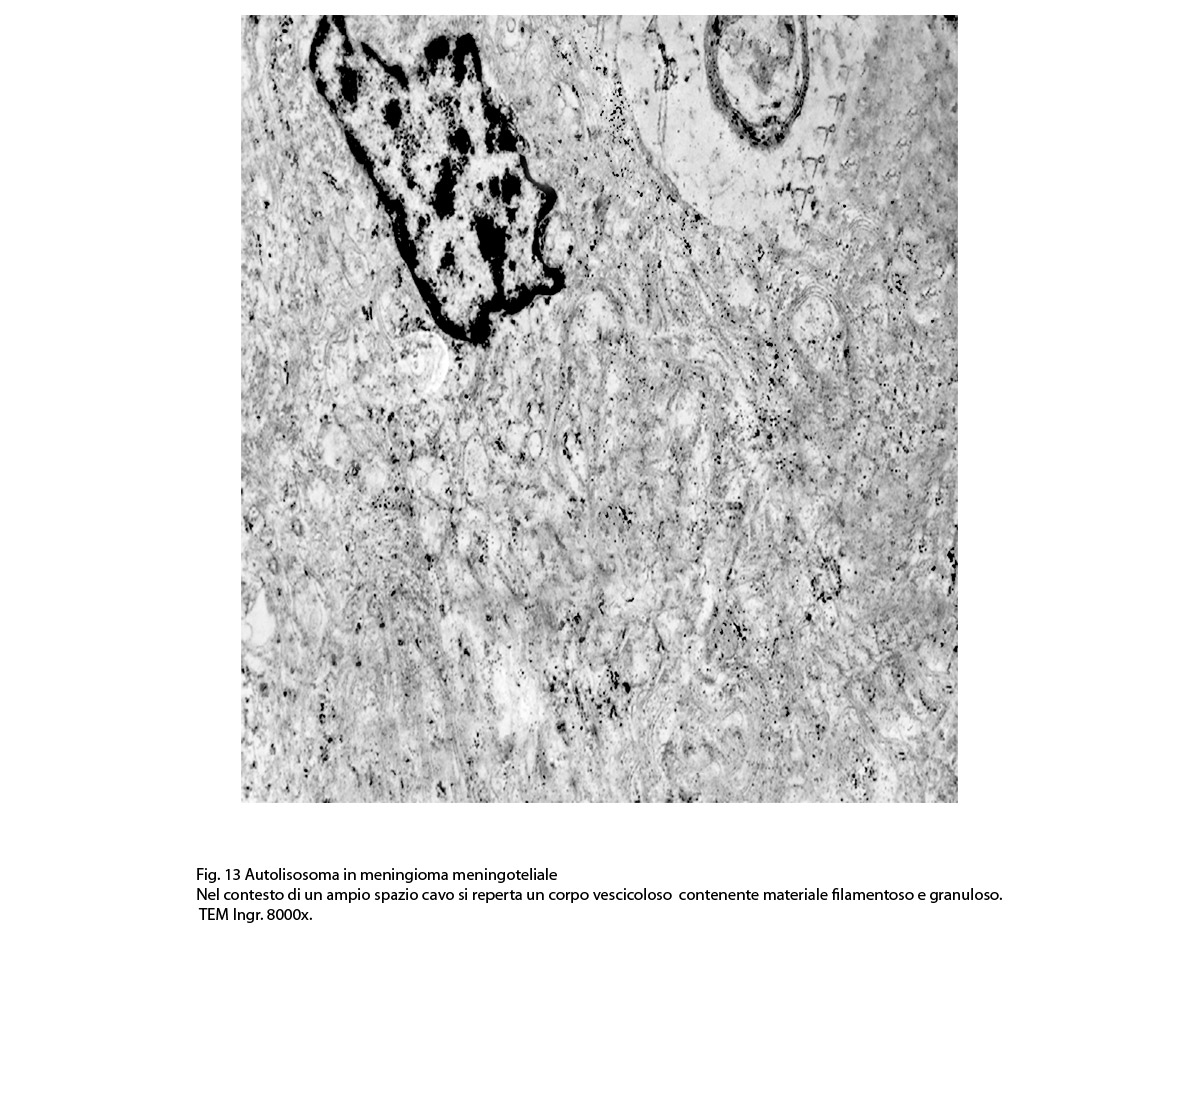

2/b AUTOLISOSOMA

Alcune cellule meningoteliali sono sedi, sopratutto a livello delle fasce periferiche, di ampie vescicole, di forma irregolare le quali sono demarcate da una membrana a mono-strato; gli spazi di queste vescicole sono in buona parte occupati da materiale amorfo, da frammenti filamentosi e da organuli intracitoplasmatici,tutto sottoposto a degradazione.

E’ possibile anche il reperto di elementi cellulari aventi il citoplasma occupato da ampie vescicole,delimitate da una membrana a monostrato, le quali sono ricolme di materiale amorfo,da strutture granulo-filamentose o da frammenti di organuli.

Non è raro il riscontro di cellule meningoteliali le quali hanno il citoplasma in buona parte occupato da una formazione cava,irregolarmente rotondeggiante; questa è delimitata da una spessa membrana ed è occupata da frammenti di citoplasma e da singoli organuli,tutto in corso di degradazione.